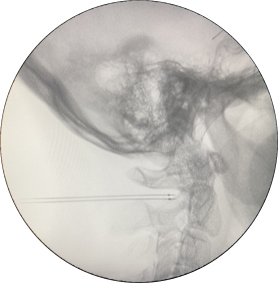

症状较轻的可以选择保守疗法,去除诱发因素,配合理疗、药物等进行治疗。如果症状较重或病史较长,应尽早到医院疼痛科就诊,明确具体的致病原因后进行针对性的治疗,如枕神经阻滞、颈2背根神经节射频等等微创介入疗法,一般都会有非常不错的治疗效果。李大爷正是通过颈2背根神经节“一针”射频解决了头痛难题。